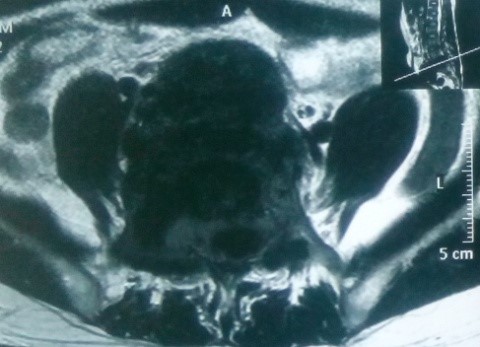

Trên MRI, khối u giảm tín hiệu xâm lấn nhiều ra phía trước vào tiểu khung, xâm lấn ra phía sau chèn ép vào ống sống. Khối u ngấm thuốc mạnh, tăng sinh mạch nhiều trên phim MRI có tiêm thuốc.

CT scanner và MRI giúp đánh giá vỏ xương, tổn thương hủy xương cũng như mức độ thâm nhiễm quanh u. Trên T1W, T2W khối u TBKL đồng tín hiệu với tổ chức cơ, có thể giảm tín hiệu do collagen và hemosiderin, T1W sau tiêm ngấm thuốc. Phần mềm quanh u có thể hoại tử nhiễm trùng, đặc điểm này thường không gặp trong nang xương phình mạch, có thể để chẩn đoán phân biệt [5,11,12]. Bệnh nhân của chúng tôi, khối u phá vỡ thân đốt L5, thâm nhiễm phầm mềm rộng chèn ép ống sống phía sau, khối u cũng thâm nhiễm rộng ra phần mềm phía trước vào tiểu khung kích thước lớn khoảng 10 x 10cm, khối u đẩy lồi và một phần ôm lấy ngã ba chủ chậu ra phía trước gây khó khăn cho việc phẫu thuật lấy bỏ khối u và là yếu tố tiên lượng tái phát cao sau mổ.